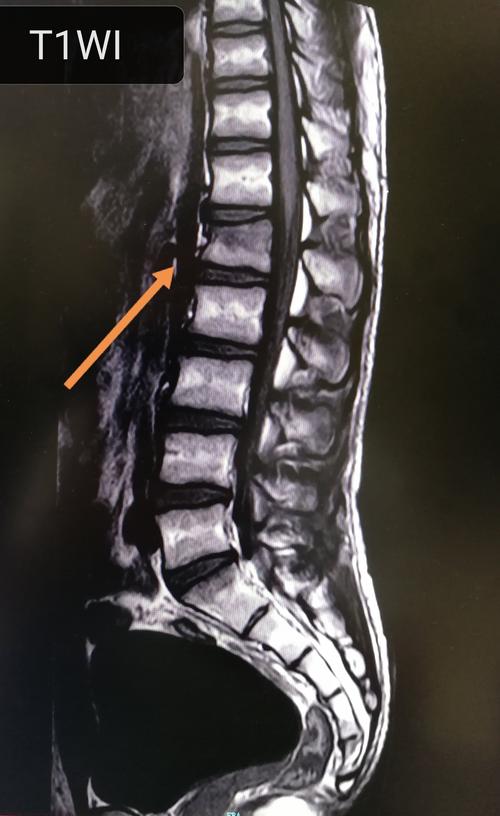

腰椎正侧位x光片:可见腰1椎体压缩性骨折 上终板塌陷,椎体前缘骨折块

腰椎压缩性骨折新鲜